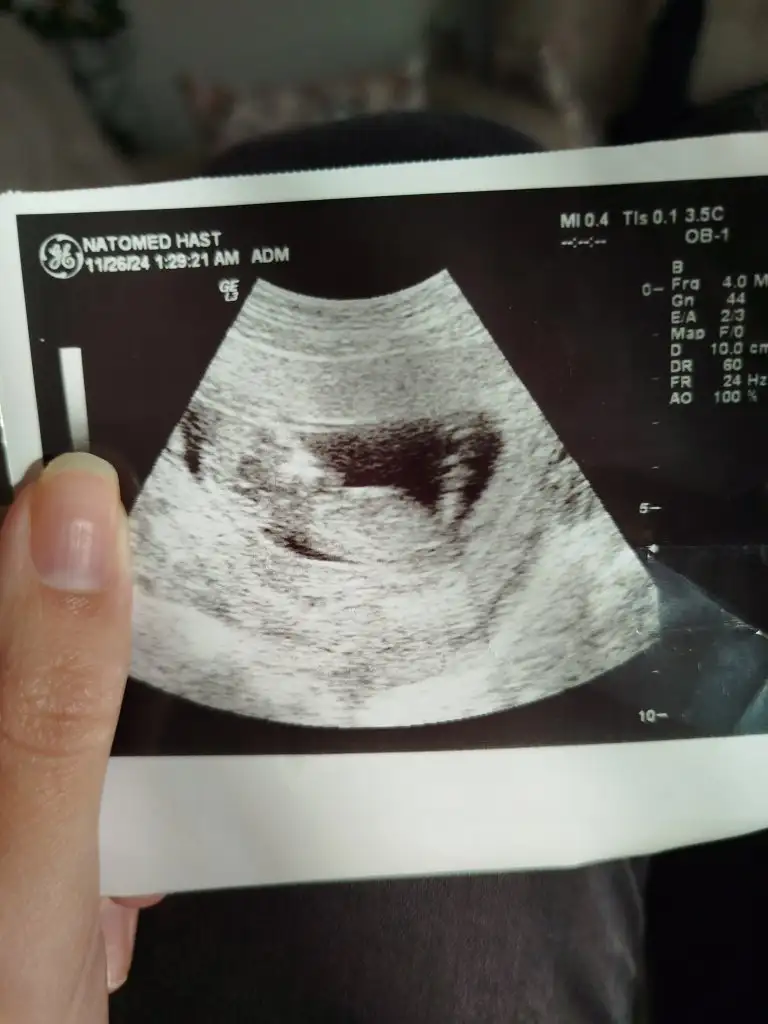

Gebelik siskinligi degil o canim, gaz ve bagirsak siskinligi :) bende hep oyle saniyordum ama bazi sabahlar iniyor dumduz ve 12. Haftamdayim hala karnim yok. Bu resimde var gibi mesela ama 2 gun sonra dumduz olmustu

Eklentiler

• IMG_20241112_111827.webp

IMG_20241112_111827.webp

8,2 KB · Görüntüleme: 152